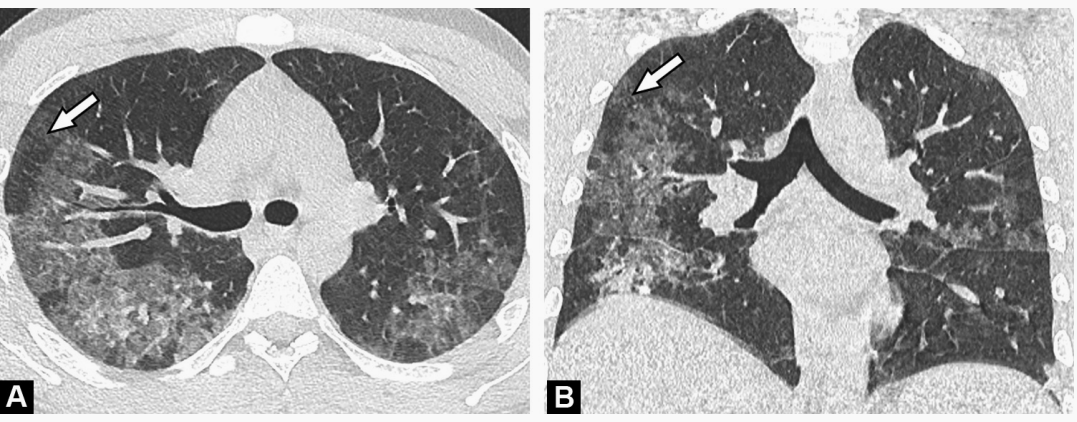

例3,新冠肺炎合并肺水肿,注意看右图B,小叶间隔增厚,并且是光滑的增厚。

例2,肺孢子菌肺炎,与新冠肺炎有时候很相似。图b显示肺孢子菌肺炎的气囊,有鉴别价值。

例3,空气潴留,马赛克衰减(箭头),提示过敏性肺炎。

例5,弥漫性肺泡出血,胸膜下病灶相对少。